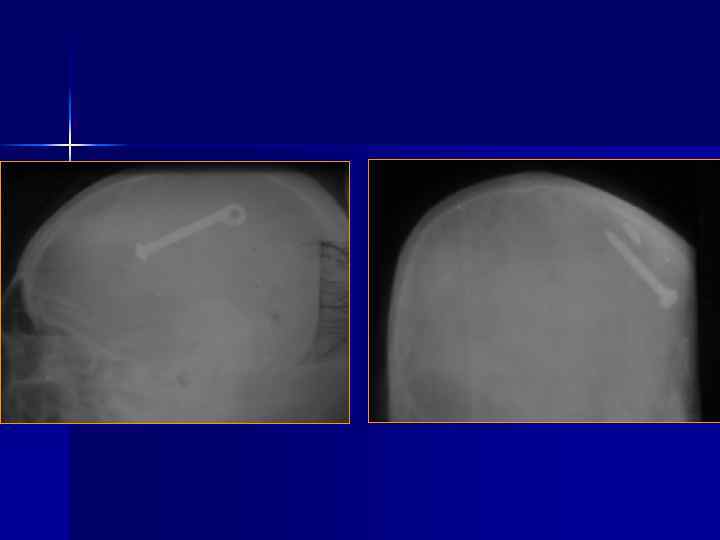

Переломы костей свода черепа N. B. -1/3 больных с тяжелой ЧМТ не имеют переломов костей. Выделяют: Линейные Вдавленные Расхождение швов Дырчатые Огнестрельные Наиболее информативна КТ, позволяющая одновременно оценить костные и внутримозговые повреждения.